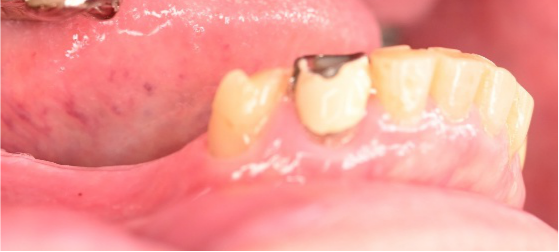

男性 Tさん 60代 (インプラント)

主訴

右上前歯が、グラグラ動く。

治療内容

歯根の周りの骨がなくなって、歯根の先端は歯肉から露出していました。保存不可能と判断し、抜歯しました。大きく骨が欠損していましたので、骨造成後、インプラントを埋入しました。

所感

長い間、大きく動揺がある状態で放置していましたので、歯根の周りは大きく骨が欠損していました。抜歯と同時に骨造成を行い、半年経過後、骨ができていることを確認してからインプラントを埋入しました。

骨造成:¥55,000(税込)

インプラント:¥363,000(税込)

合計:¥418,000(税込)

Before

After